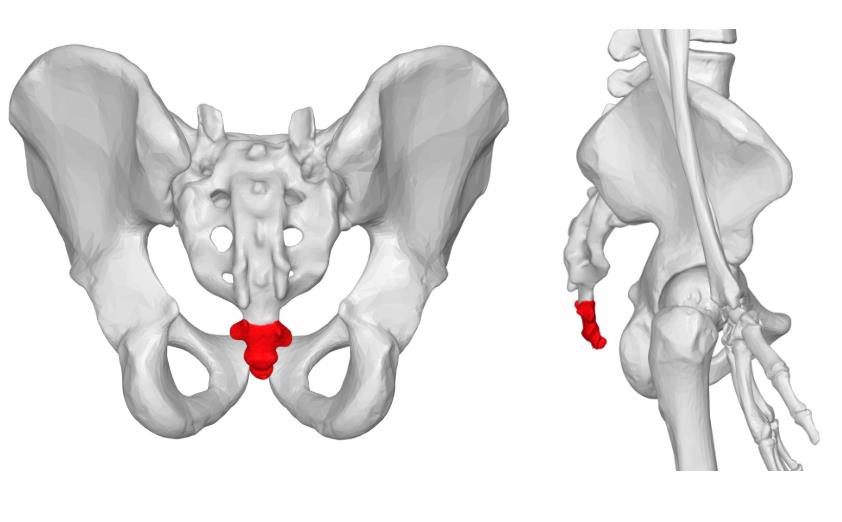

꼬리뼈

꼬리뼈는 미골, 미저골 이라고 부르는데요, 영어로는 coccyx 라고 표기 합니다.

꼬리뼈는 원래 사람은 꼬리가 있었지만 점점 진화하면서 이 부분이 퇴화되어 그 흔적으로 꼬리뼈라는게 남아 이름이 붙여졌다고 알려져있죠.